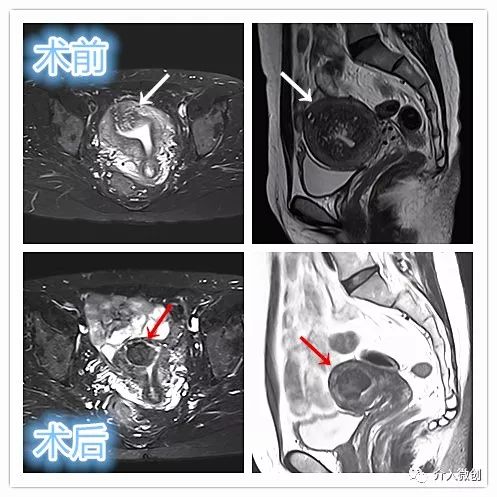

子宫腺肌瘤

中年患者,患有“子宫腺肌瘤”7年余,长期受痛经、月经量增多困扰,严重影响生活质量。经多处求医,经历药物调理、“曼月乐”宫腔植入、“海扶刀”消融术等多种治疗,痛经、月经量多等情况一直无法有效缓解,日渐严重。经UAE治疗后,术后痛经、月经量增多等症状迅速得到缓解,生活质量明显改善。术后3月上述症状基本消失。

- 术前子宫MRI提示宫腔明显增大,诊断为“子宫腺肌瘤”。

- 术后4个月复查,子宫明显缩小,腺肌瘤明显坏死吸收,相关症状基本消失。